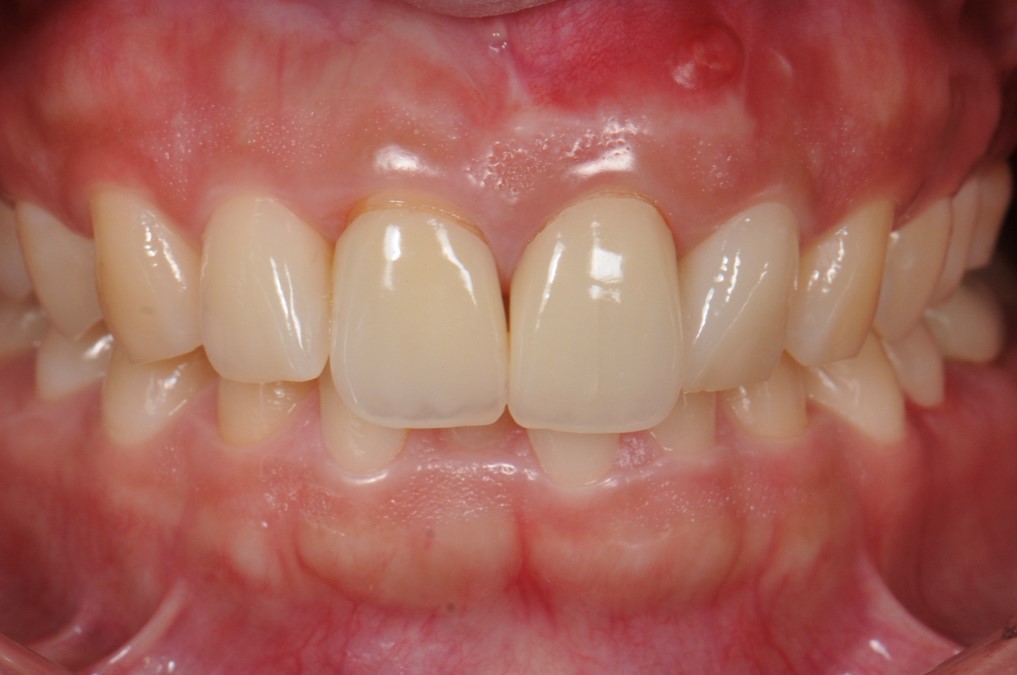

case3 症例(セラミッククラウン・ラミネートべニア前歯)

治療前

治療後

| 費用(税込み) | セラミッククラウン:154,000円×4本+ポンティック66,000円 |

|---|---|

| メリット・デメリット | 歯を削る歯質を削合する必要がある |

| 治療回数 | 5-6回(根管治療は別) |

| 主訴 | 歯の形態をきれいにしたい |